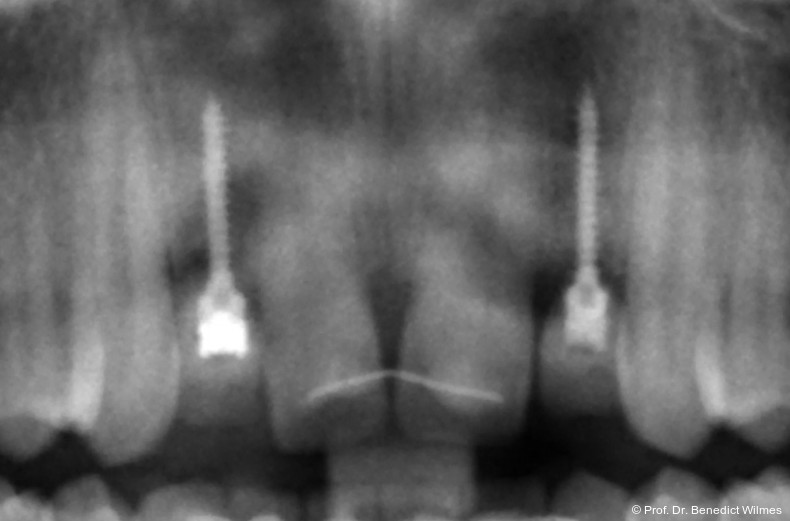

Ein 14-jähriger Patient wurde bei Aplasie der beiden oberen seitlichen Schneidezähne mit dem Ziel der beidseitigen Lückenöffnung kieferorthopädisch therapiert (Abb. 1a+b). Zum Ende der kieferorthopädischen Behandlung wurden zwei Miniimplantate in Regio 2er als temporärer Zahnersatz inseriert (Benefit System, PSM, 2 x 13 mm, Abb. 2a+b). Nach Abdrucknahme wurden Kronen auf den Peek-Abutments modelliert und diese mit Kunststoff auf die Abutments geklebt (Abb. 3a–d). In den Abbildungen 3 und 4 sind die klinischen und röntgenologischen Nachkontrollen innerhalb der nächsten achteinhalb Jahre dokumentiert. Man erkennt einen sowohl in der Höhe als auch in bukkopalatinalen Breite verbleibenden gesunden Knochen ohne Anzeichen einer Atrophie. Im Alter von 23 Jahren wurden die definitiven Implantate ohne die Notwendigkeit einer Augmentation eingesetzt (Abb. 5) und nach Einheilung prothetisch versorgt (Abb. 6a–e und Abb. 7a–c).

Nach Abschluss der kieferorthopädischen Pfeilerverteilung wurden zwei Miniimplantate in Regio 3er inseriert (2 x 13 mm). Nach Herstellung im Labor wurden Kronen auf den Miniimplantaten aufgeschraubt (Abb. 13+16a–d). Auch hier wurde darauf geachtet, dass die Kronen aus der Okklusion geschliffen wurden (Abb. 14). Bei den Nachkontrollen zeigten sich ebenfalls stabile Miniimplantate und ein entzündungsfreies Implantatlager ohne erkennbare Atrophie des Knochens (Abb. 15 und 16a–d).